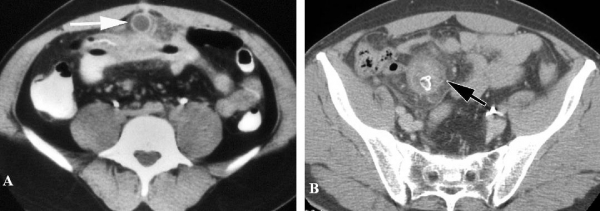

Hình 26: Túi thừa Meckel lộn ngược ở bệnh nhân nam 31 tuổi. A, CT uống và tiêm cản quang, thấy khối lồng hồi manh tràng, có “target sign” (đầu mũi tên). B, Vùng trung tâm là lõi dài đậm độ mỡ (mũi tên. Sau mổ là túi thừa Meckel lộn ngược . (Angela D. Levy, Christine M. Hobbs (2004). Meckel Diverticulum: Radiologic Features with Pathologic Correlation. RadioGraphics 24:583).